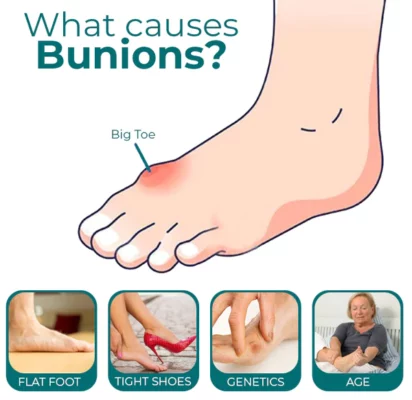

When you have bunions or overlapping toes, long days on your feet can be quite painful. By entering and soothing the underlying tissue to lessen hurting and discomfort, the RASSMAM™ BunionOut Relief Patch can assist in providing that pain relief in a natural way.

- RASSMAM™ BunionOut Relief Patch are made to straighten your big toe and put it back in its proper place. It not only relieves your toe from the pain, swelling, and pressure brought on by bunions, but it also aids in reducing the bunion so that the joint won’t become misaligned once again. Relieve pain and overlapping toes without surgery.